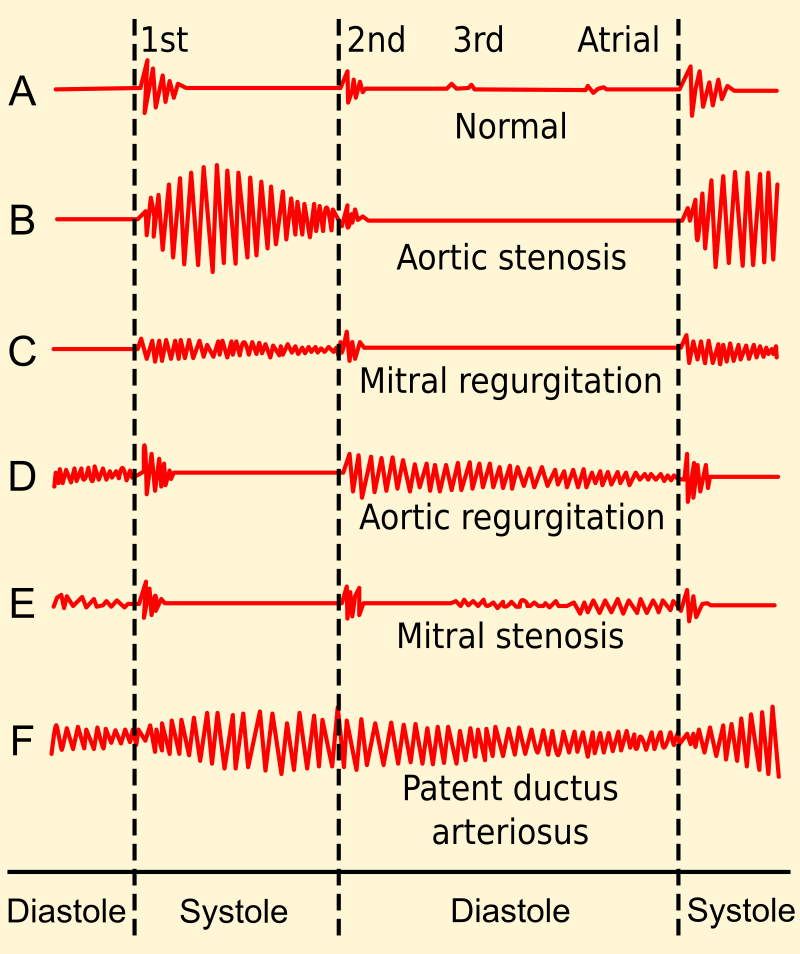

Aortic stenosis causes a crescendo-decrescendo murmur after a systolic ejection click.

Clinical features of aortic regurgitation include an early, blowing diastolic murmur and hyperdynamic circulation due to increased pulse pressure.

- A holosystolic blowing murmur that becomes louder with squatting due to higher systemic resistance

- An opening snap followed by a diastolic rumbling